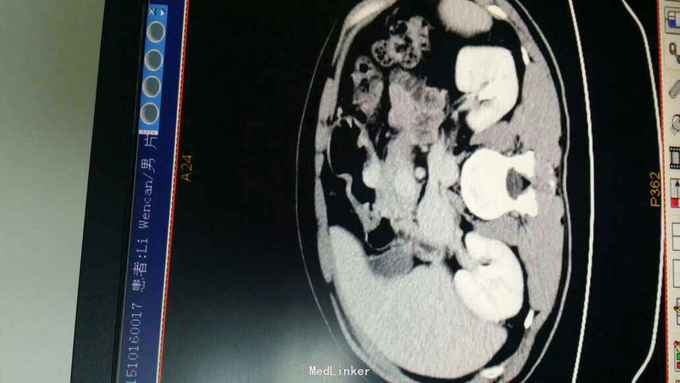

查体:T:36.8 ℃ P 85次/分 R:22 次/分 BP 119/79 mmHg 皮肤、巩膜无黄染,心、肺听诊无异常。腹部平坦,未见胃肠型及胃肠蠕动波,无腹壁静脉怒张,腹式呼吸活动不受限,腹肌柔软,全腹无压痛及反跳痛,肝区无压痛,肝浊音界位置正常,肝脾未触及,Murphy征(-),移动性浊音(-),双肾区无压痛及叩痛,肠鸣音正常,未闻及血管杂音。 辅助检查:1.血常规:WBC 7.9x109 /L,HGB 133 g/L,N 68.8%; 2.肝功能:TBIL 13.2μmol/L,DBIL 4.4μmol/L,TP 71.7g/L,ALB 44.3g/L,ALT 16U/L,AST 19U/L,GGT 15U/L,GLU 5.03mmol/L; 3.肿瘤标记物:CA199:38.64 U/ml,AFP、CEA、TPSA 未见异常。 4.胃镜+病理:胃体后壁溃疡,3.5cm×4cm,病理:(胃体)中分化腺癌,HP-。 5.全腹CT:胃体近胃窦处后壁局部组织不规则增厚。肝胆胰脾肾未见异常;右肺下叶背段肺大泡。

诊断:胃癌 治疗:入院后行常规术前检查,术前准备完善后在气管内插管全麻下行腹腔镜胃癌根治术,术中探查肝脏及腹腔其它部位未见明显肿瘤转移。肿瘤位于胃体近胃窦处后壁,肿瘤侵出浆膜,与胰腺被膜少许粘连。腔镜下行远端胃大部切除术,清除胃周围淋巴结,于腔镜下行结肠前胃空肠端侧吻合(毕Ⅱ式吻合) 。手术顺利,术后恢复好,术后第4天拔除胃管,第5天进食流质饮食,术后1周出院。术后病理报告:胃中分化腺癌,覃伞型,3.5cm×4cm,侵润胃壁全层,近、远两切缘未见癌累及。淋巴结见转移癌(第一组0/0,第八组0/2,第十一组0/0,胃小弯侧12/14,胃大弯侧8/9,大网膜0/0)。免疫组化结果尚未回报,待免疫组化结果回报后再行综合治疗。